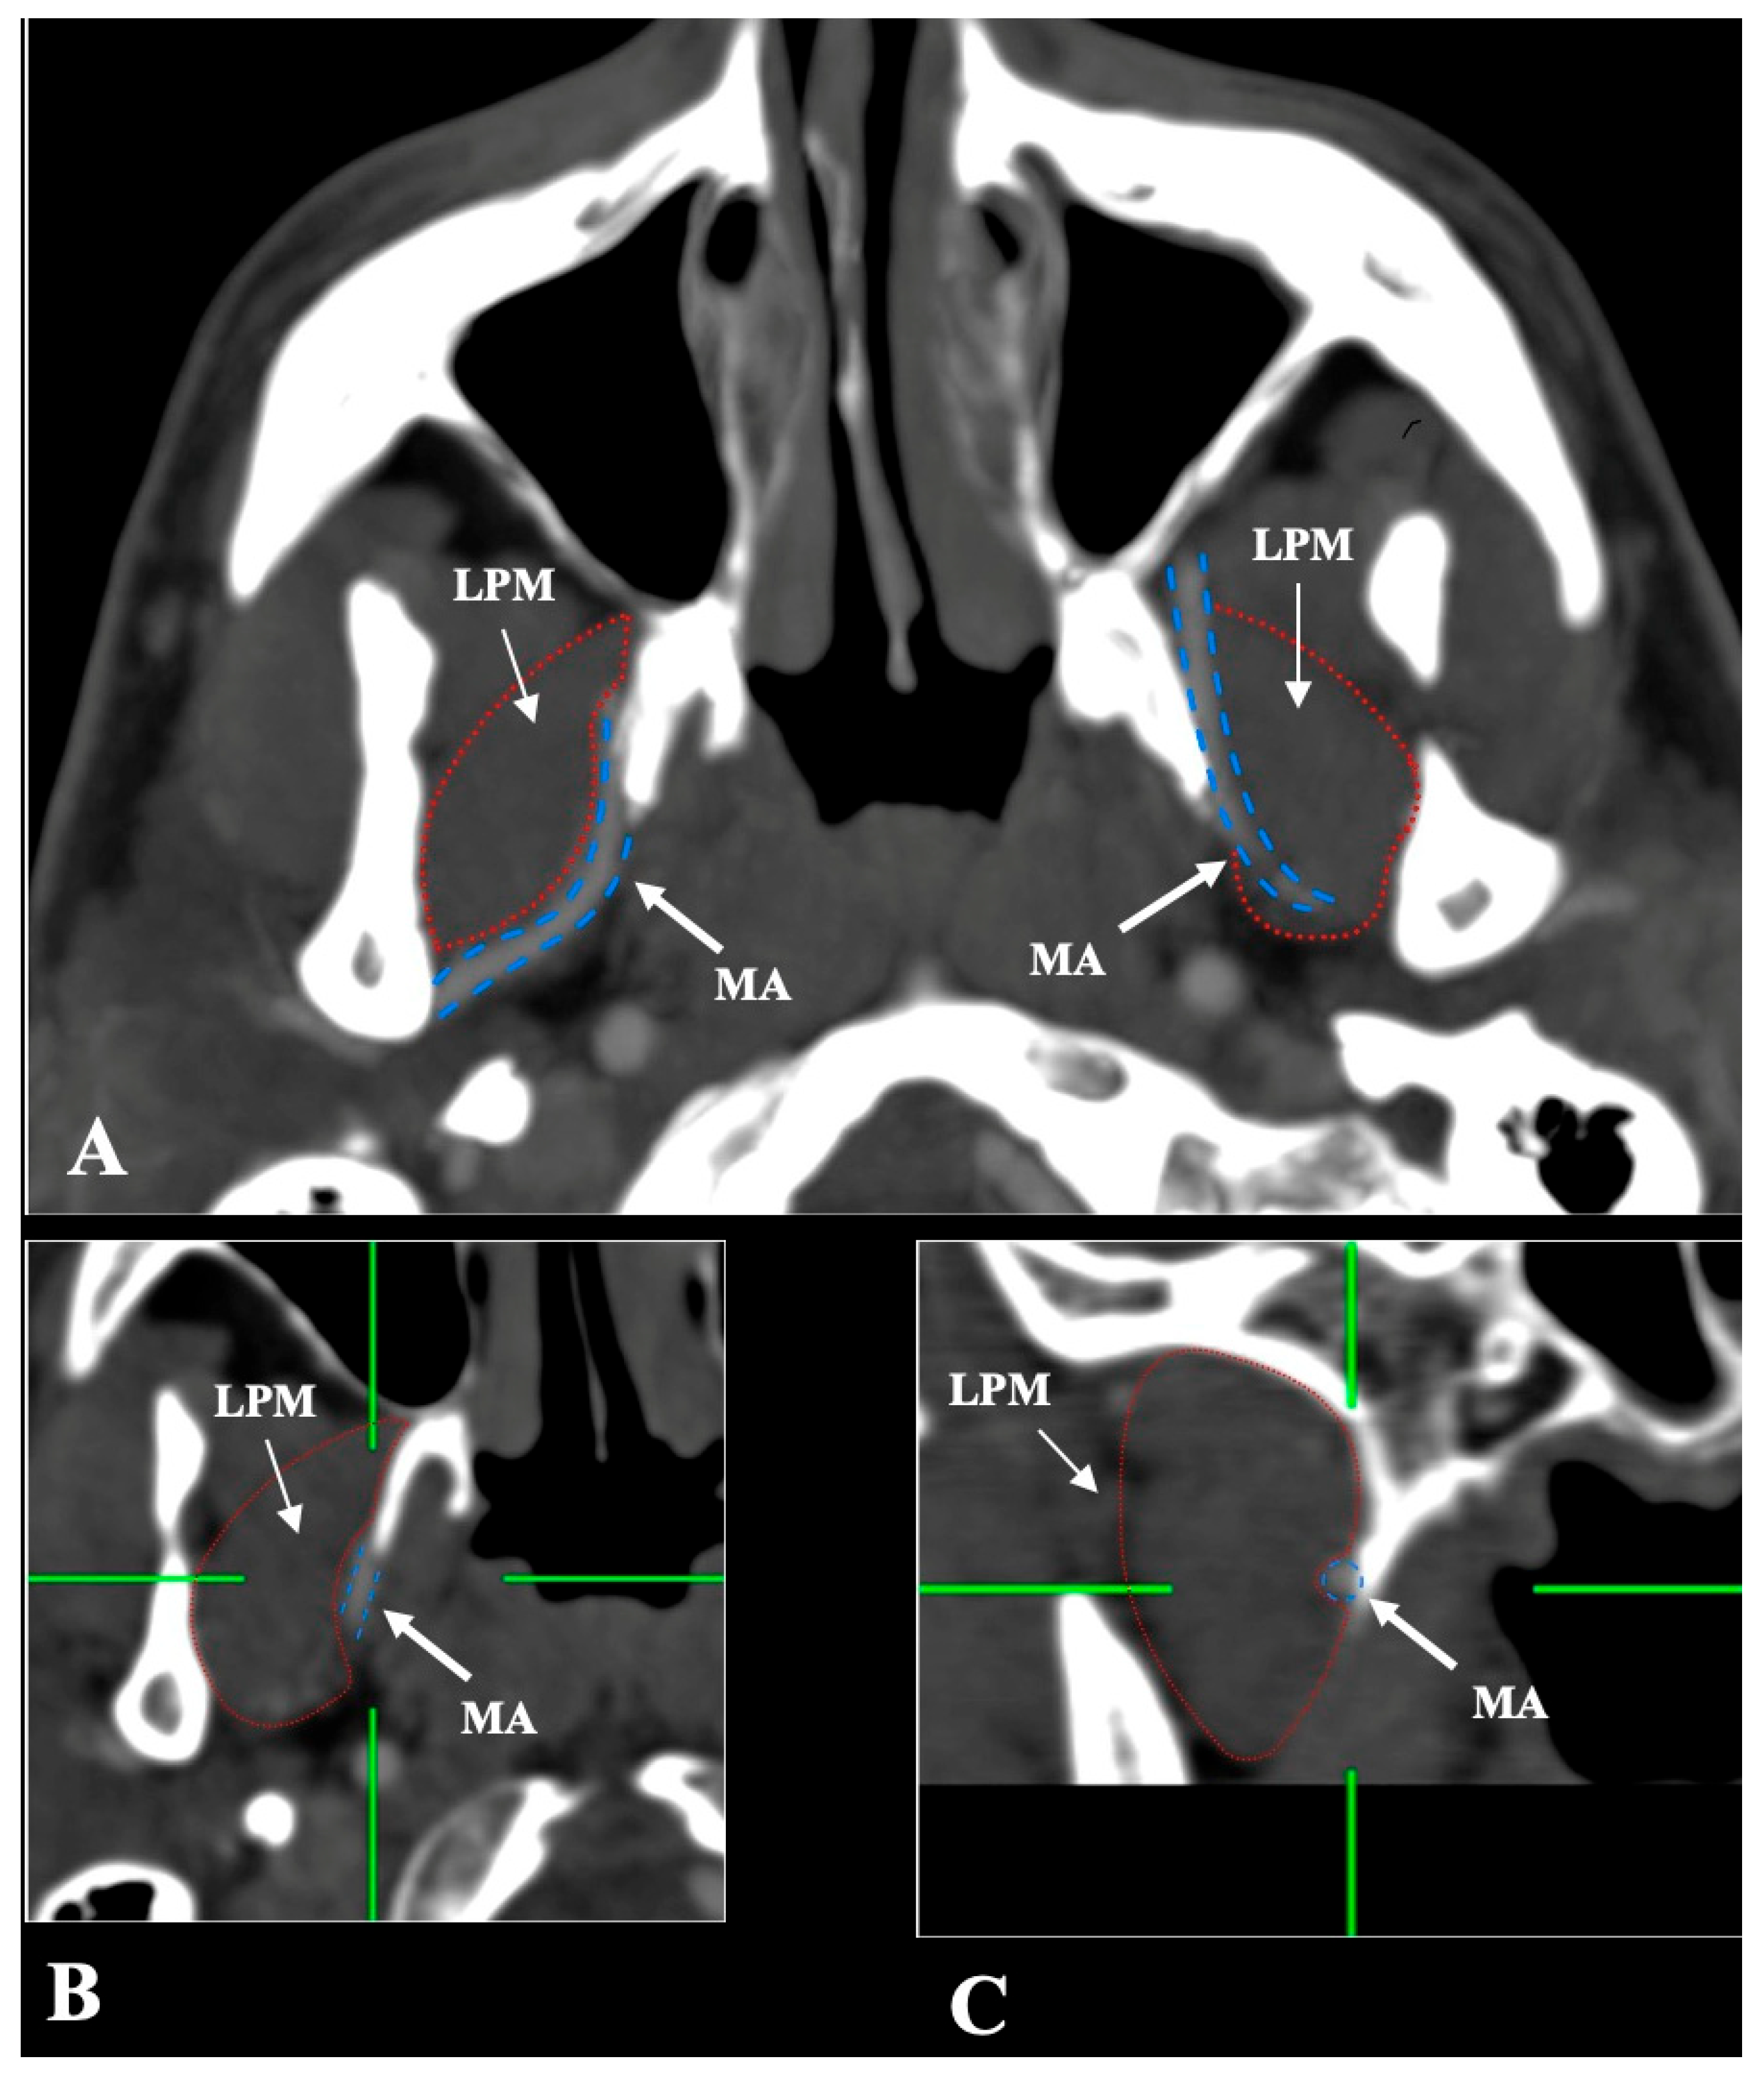

- Medial (deep) to the LPM: Identified in 148 sides (29.6%), best appreciated on axial and coronal reconstructions (Figure 3).